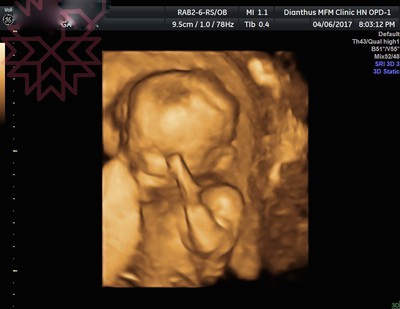

[14w&17w]小樂性別開獎!

第二胎比較混哦,已經跳過二次產檢沒記錄囉!!! :P前二次產檢分別在14w及17w時進行,最大的消息就是寶寶性別開獎啦!!!!14w那次產檢我沒有期望一定看得到,但也是進了診間我就主動詢問可否看性別,...